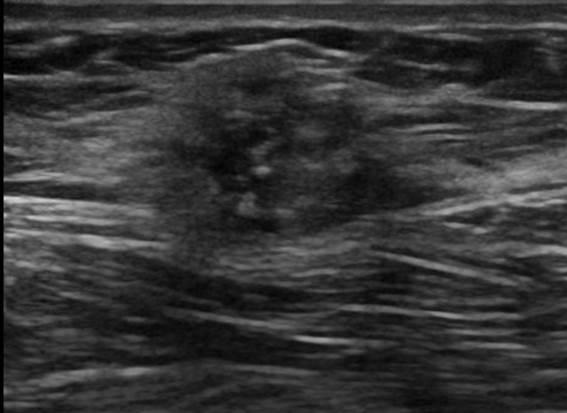

Ung thư vú

» Thông tin: Nữ giới – 41 tuổi.

» Lâm sàng: Khối tuyến vú.